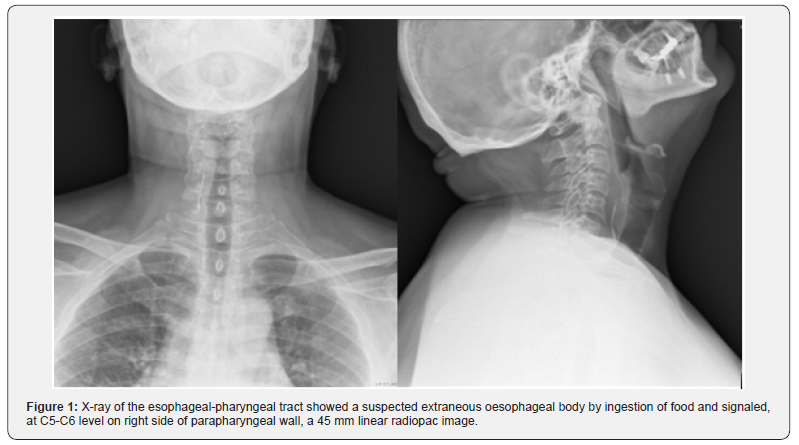

50-year-old men, V.F., presented to our ENT department due to a severe dysphagia that appeared about 5 days earlier after a fish-based lunch. The patient was convinced he had ingested a fish hook. The endoscopic evaluation of the high airways showed an important edema of the right arytenoid; the vocal cords were normal in form and motility, and no foreign body was visible. However, the X-ray of the esophageal-pharyngeal tract Figure 1 showed a suspected extraneous oesophageal body by ingestion of food and signaled, at C5-C6 level on right side of parapharyngeal wall, a 45 mm linear radiopac image. An integration with endoscopic examination was required. However, esophagogastroduodenoscopy was negative for the presence of foreign bodies,but it showed the presence of an extraneous granuloma at the level of the right arytenoid.In the same day, in general anesthesia, apanendoscopy of the superior aero-digestive tract was performed, which does not show any extraneous body at this level, except an important congestion of the right piriform sinus. At the end of the procedure, a nasal-gastric tube was due to a suspected perforation of the esophagus. At this point, the hypothesis that the right piriform sinus was been the point of entry of the foreign body became more and more concrete.A TC scan of the neck (Figure 2) was performed and it highlighted the foreign body at the right side of parapharyngeal wall, at the height of the homolateralarytenoid. Therefore, we decided to undergo a cervicotomicsurgery. In general anesthesia, cutaneous incision was performed along the margin of the sternocleidomastoid muscle, about 10 cm. The right thyroid lobe was found and lowered from the lateral wall of the trachea to the side wall of the esophagus, which had a millimetric puncture (foreign body output point). In the tracheo-esophageal sulcus, near the right recurrent nerve, the foreign body (metal wire about 5 cm in length) Figure 3 was found and removed.